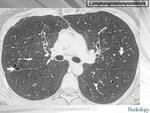

лимфангиолейомиоматоз

Типичный пример патологии при которой основным патерном являются кисты - :

материал взят со статьи Dr.Mario

http://www.radiomed.ru/publications/luchevaya-diagnostika-diffuznykh-interstitsialnykh-zabolevanii-legkikh-dizl-obshchie--0

Лимфангиомиоматоз.

Из архива AFIP. Лимфангиолейомиоматоз.